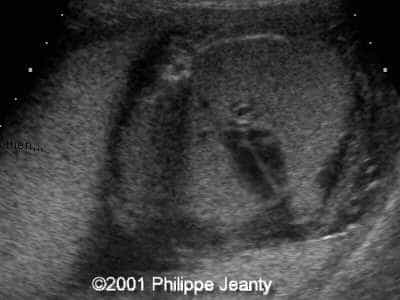

This 2nd trimester fetus has the following images (actually, these images remained unchanged for several weeks)

• very enlarged lungs on both sides

• inversion of the diaphragm that is convex towards the abdomen

• small compressed heart

• ascites but no generalized hydrops (no skin thickening for instance)

A much more common diagnosis for a bilateral echogenic lung associated with microcardia and ascites (Budd-Chiari phenomenon) is Larynx, atresia or as reported by several the CHAOS syndrome which stands for Congenital High Airway Obstruction Syndrome (which is typically laryngeal or tracheal atresia). This is the diagnosis that was indeed suspected in this fetus.